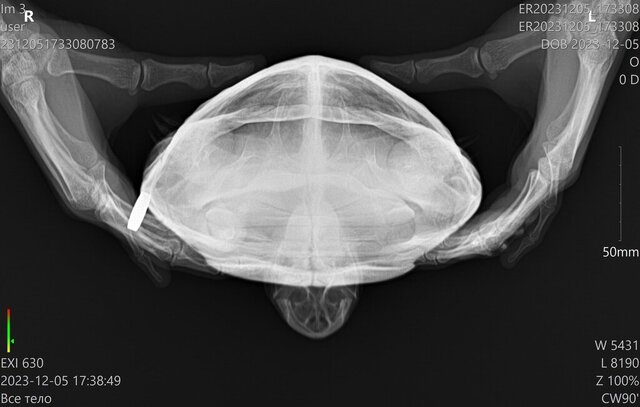

Сделали рентген, предварительный диагноз - пневмония. Укололи Энроксил и Элеовит, через час черепаха очень вялая была, спала, на прикосновения не реагировала, но к утру активность вернулась

Не могли бы вы посмотреть рентген и назначения? Хотелось бы убедиться, что можно продолжать лечение   по этой схеме857955925_WhatsAppImage2023-12-06at09_16_05.thumb.jpeg.5e6ec42bf0c6add2ebb8df78cf6187ff.jpeg1540015184_ER20231205_173308_ER20231205_173308__05-12-202317_38_49_1-3(1).thumb.jpg.599338906b0ed89dfb86f8237ae1f926.jpg1270917588_ER20231205_173308_ER20231205_173308__05-12-202317_35_20_1-2(1).thumb.jpg.5b554520fd66f625d542af4cb855f73d.jpg

@Zefa по снимкам да, лёгкие мутные

Назначения Вам сделали правильные и по дозировкам и по препаратам. После укола черепаха вялая - это реакция на антибиотик, т.к. дозировка для режима через день. Если ей прям так плохо после укола, то можете колоть 0.11мл, но каждый день, начиная со дня, когда нужно следующий укол делать.